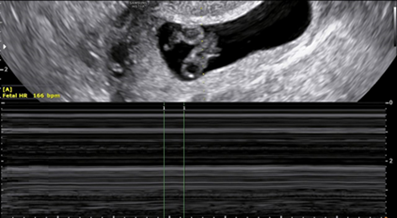

The case of a 27-year-old primiparous women who presented at 7 weeks with features of hyperemesis in a routine pregnancy follow up is presented. No previous ultrasonographic imaging was done. Current ultrasound scan showed a twin live intrauterine pregnancy with thick separating membrane giving a lambda sign. Crown Rump Length (CRL) of fetus A measured 1.32 mm with Fetal Heart Rate (FHR) at 166 Beats Per Minute (BPM) and the CRL of fetus B was 1.15 mm with FHR 154 BPM. It also showed a gestational sac with a fetal pole with CRL 10 mm in the right ovary complicated by a surrounding peri-ovarian hematoma forming a right adnexal mass measuring 57×35 mm. No cardiac activity was seen in this fetal pole (Figure 1 A/B).